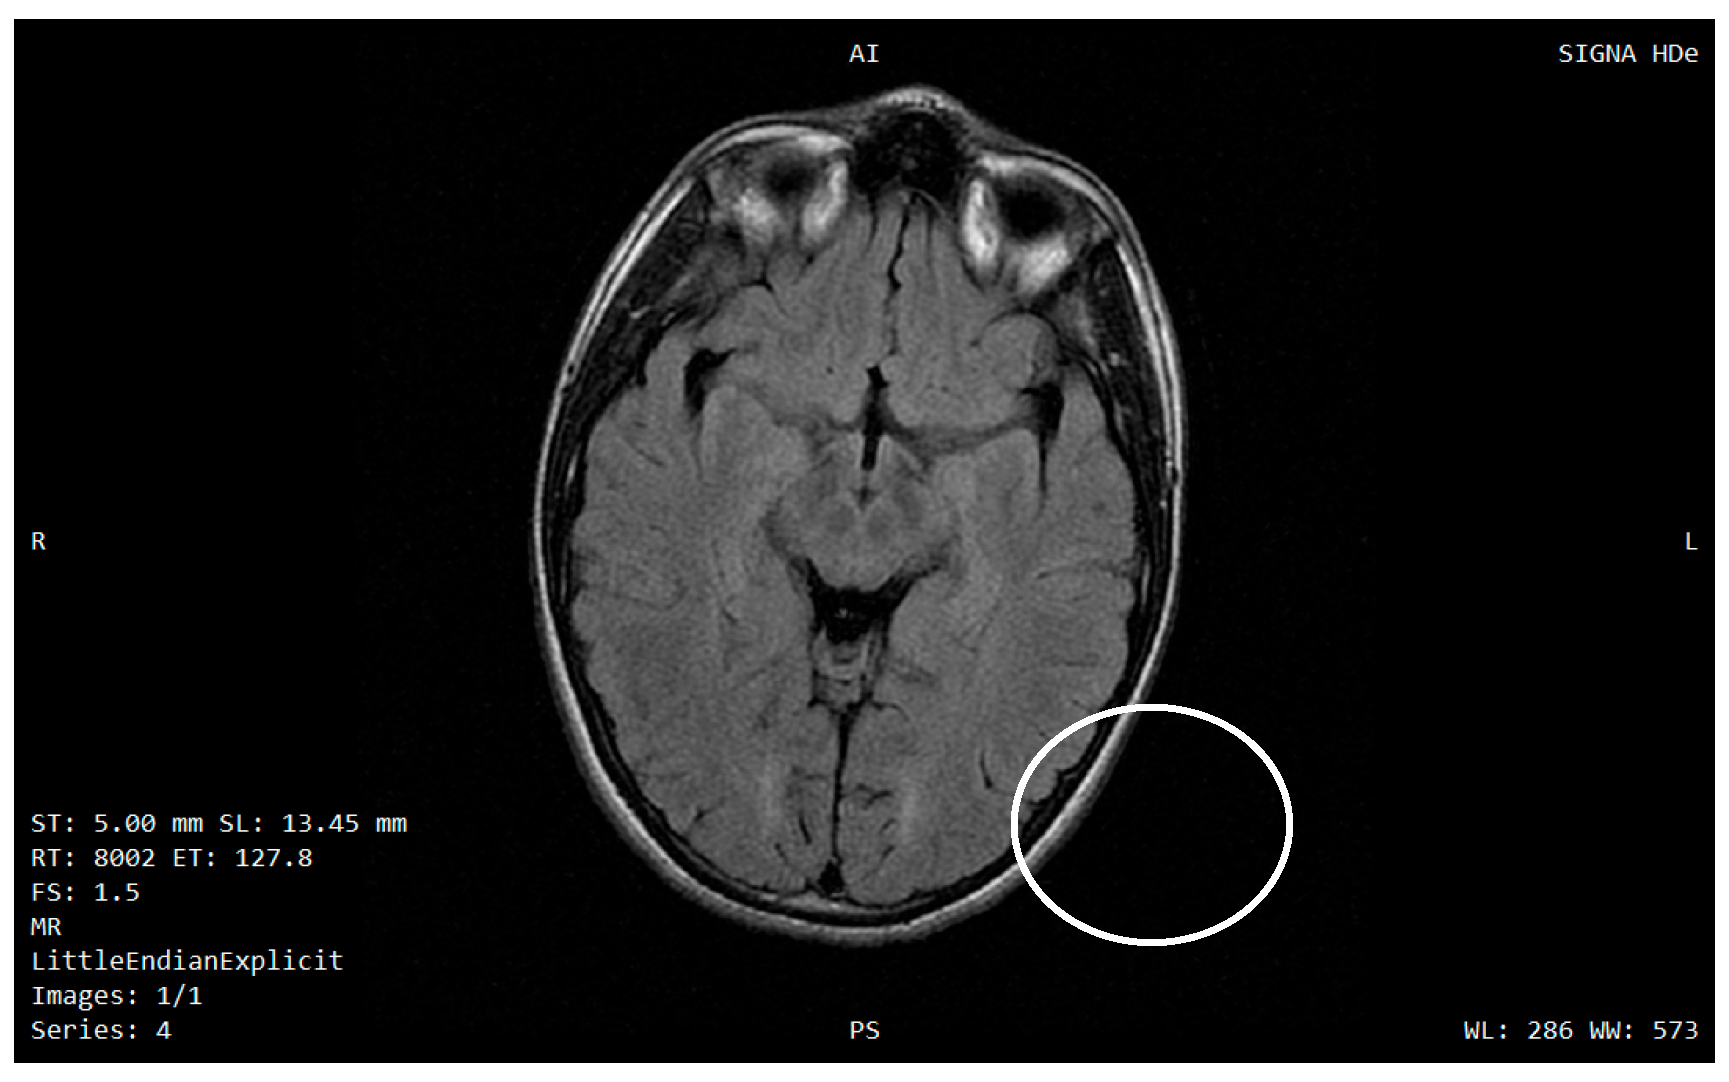

- Samara, A.; Lugar, H.M.; Hershey, T.; Shimony, J.S. Longitudinal assessment of neuroradiologic features in Wolfram syndrome. AJNR Am. J. Neuroradiol. 2020, 41, 2364–2369. [Google Scholar] [CrossRef]

- Lugar, H.M.; Koller, J.M.; Rutlin, J.; Eisenstein, S.A.; Neyman, O.; Narayanan, A.; Chen, L.; Shimony, J.S.; Hershey, T. Evidence for altered neurodevelopment and neurodegeneration in Wolfram syndrome using longitudinal morphometry. Sci. Rep. 2019, 9, 6010. [Google Scholar] [CrossRef] [PubMed]

- Hershey, T.; Lugar, H.M.; Shimony, J.S.; Rutlin, J.; Koller, J.M.; Perantie, D.C.; Paciorkowski, A.R.; Eisenstein, S.A.; Permutt, M.A. Early brain vulnerability in Wolfram syndrome. PLoS ONE 2012, 7, e40604. [Google Scholar] [CrossRef] [PubMed]